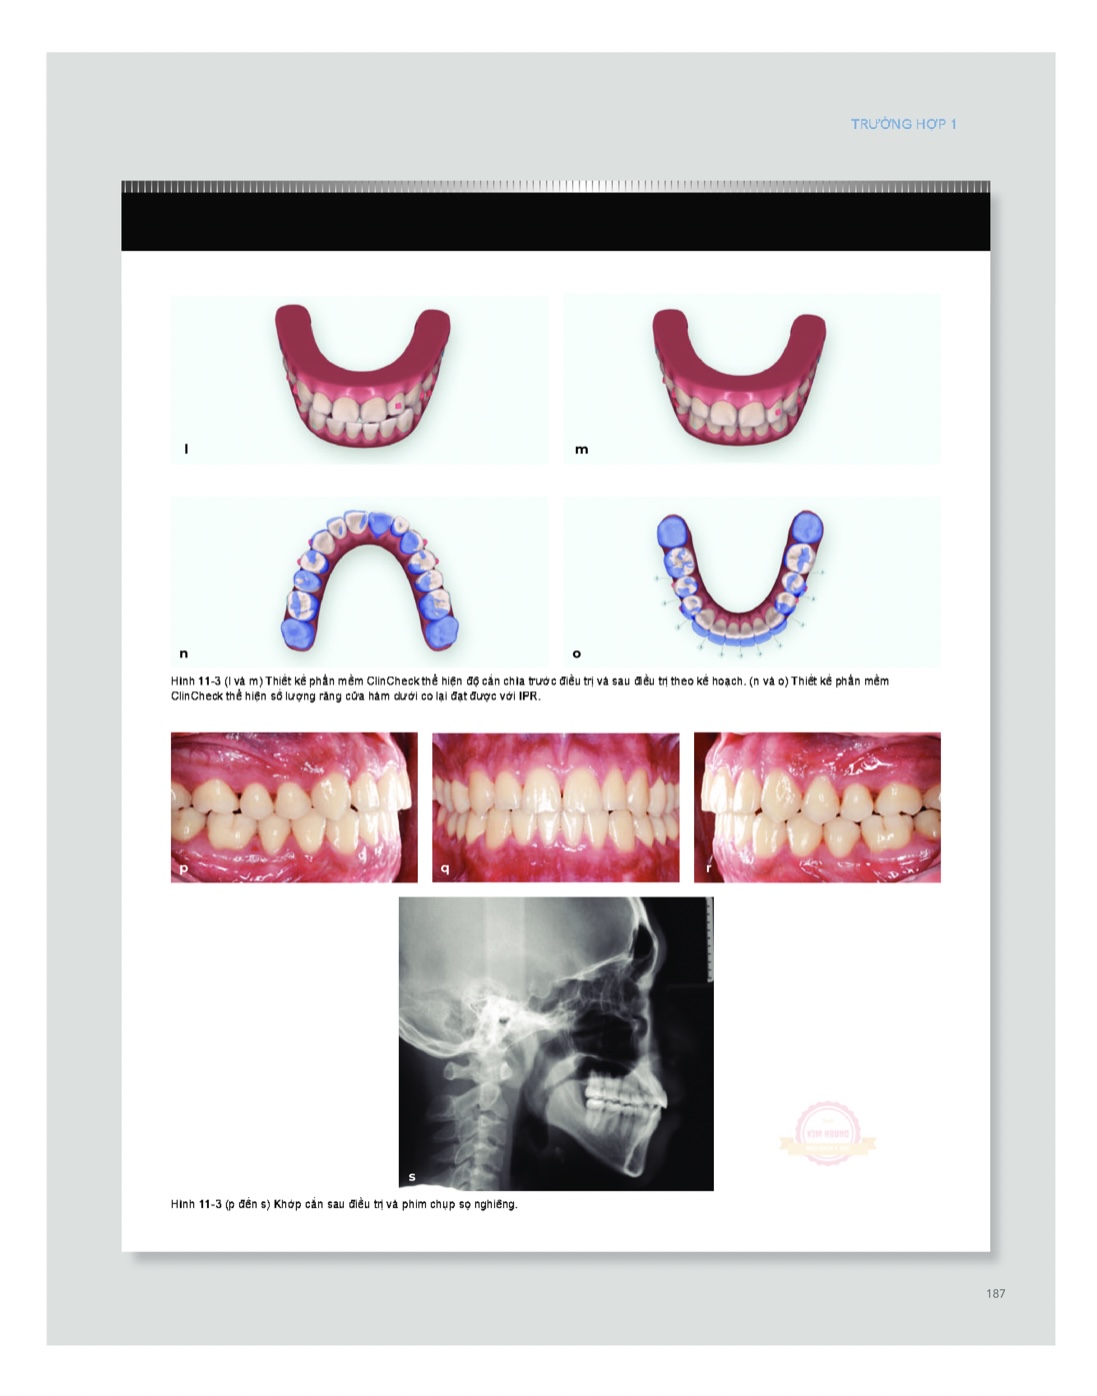

Kỹ thuật chỉnh nha khay trong suốt (Phần 2)